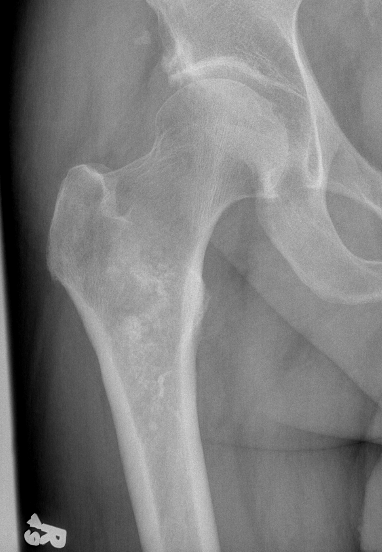

X-ray

Lytic lesion with punctate or spotty calcification

Worrisome features

- growth over time

- large > 5cm

- endosteal scalloping is hallmark of chondrosarcoma

Large calcification with endosteal scalloping humerus